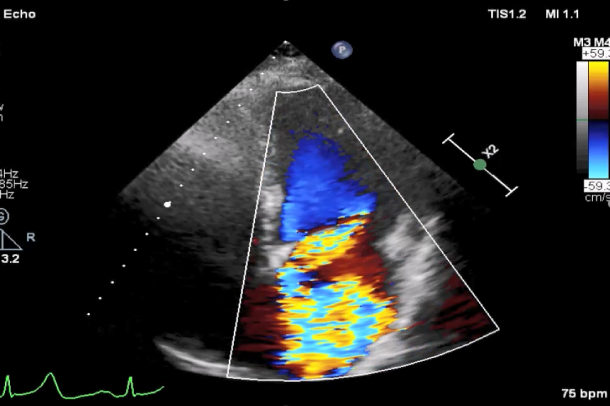

TEE短轴脱垂区域显示(P2、P3区大范围脱垂)

TEE短轴脱垂区域显示(color,血流来源于P2、P3区)

肺静脉收缩期反向血流

患者麻醉方式同样采取全麻,建立静脉通路后,穿刺右侧股静脉后,预埋ProGlide缝合器后,送导管至房间隔部位,成功穿刺房间隔后进入左房,调整导管角度,顺利到达二尖瓣目标位置,后在X线及食道超声联合辅助下,宋光远教授使用2枚XTR二尖瓣夹,在精确定位后,准确夹合二尖瓣A2-P2以及A3-P3区域,患者收缩压即刻上升30mmHg,左心房收缩压由62mmHg下降至28mmHg,术中测反流面积明显减少,肺静脉多普勒波形由反向恢复正常。手术顺利结束,术后患者即刻苏醒,安返病房。